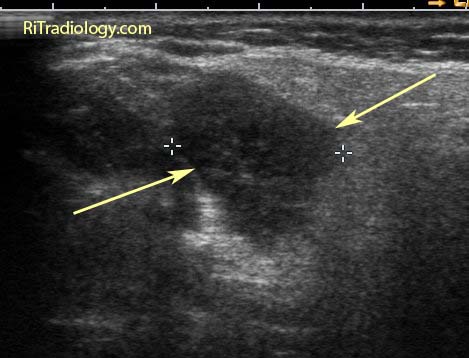

Non-contrast CT confirms the presence of a nodule in the left lower lobe (arrow) that contains a central calcification.

Our case: benign nodule, likely a granuloma.